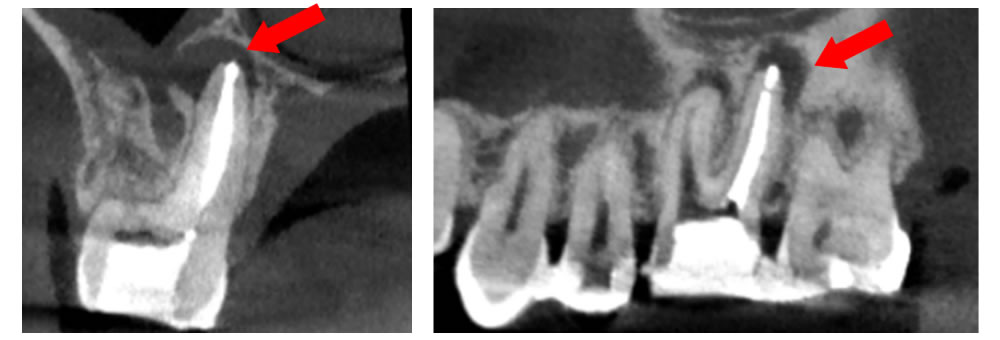

CTでの根管精密検査

根管内は非常に複雑な形状をしているため、レントゲンだけでは、全てを把握する事が出来ません。特に、歯根の先端に膿が溜まる病変などはレントゲンに写らない事も多く、歯の痛みや違和感を感じながらも、どこに原因があるのか分からないと言う状況になる事も少なくありません。

根管内は非常に複雑な形状をしているため、レントゲンだけでは、全てを把握する事が出来ません。特に、歯根の先端に膿が溜まる病変などはレントゲンに写らない事も多く、歯の痛みや違和感を感じながらも、どこに原因があるのか分からないと言う状況になる事も少なくありません。

そのため当院では、歯科用CTでの3次元精密検査を実施しています。レントゲンでは写らない病巣の発見や、見落としがちな根管の把握が出来るため、原因の早期発見、悪化防止が適切に行えます。

▲他の歯科医院での根の治療

▲当院でやり直した治療

他の医院で根の治療を行った患者様が「痛みを感じる」と来院された例があります。診察すると、治療を受けた部分は歯の先端まで白い充填物が入っておらず隙間だらけで、先端に膿が溜まっていました。そこで当院は根の先端まで隙間なく白い充填物を入れて痛みを消失させました。ここで可能であれば、歯を長期使用するためにしっかりした被せ物をします。被せ物は充填物同様、その歯の予後を左右する大事な要因となります。

空洞に挟まったハリを除去することが可能

過去に他の医院で治療した際の折れたハリ(赤丸)が入っているレントゲン。

ハリを除去し、徹底的に洗浄したレントゲン。

空洞を根の先までしっかり埋めたレントゲン。

根の治療はハリを使用するため、ハリが折れて空洞の中に挟まってしまうケースがあります。これは治療の特性上、どうしても起こりうることなのですが、隙間を埋めることができずに空洞があると、しっかり洗浄されていないため、そこが痛み始めたらどうすることもできません。しかし、当院ではその根の中の細かい空洞に挟まったハリを除去し、治療することが可能です。ある患者様が半年以上もジンジンする痛みに悩まされ、いくつかの医院に行かれたそうですが治せる医院がなく、諦めかけていたそうです。しかし、当院にお越しいただいてハリを除去し治療を行ったところ、3回の通院のみで痛みを完全になくすことができました。

【術後のCT画像】